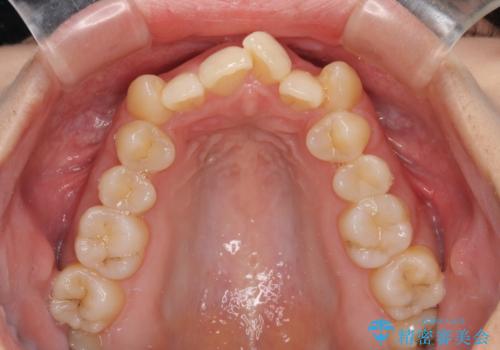

八重歯を改善 ワイヤー装置での抜歯矯正

- 目立つ八重歯を気にして来院された患者様です。

下顎歯列の叢生は軽度であることと、口元の突出感が全くなかったことから、八重歯解消のために上顎左右第一小臼歯を抜歯し、ワイヤー装置にて矯正治療を行うこととしました。